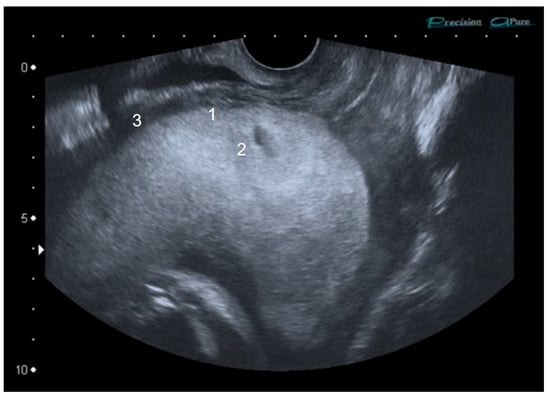

2. Case Report